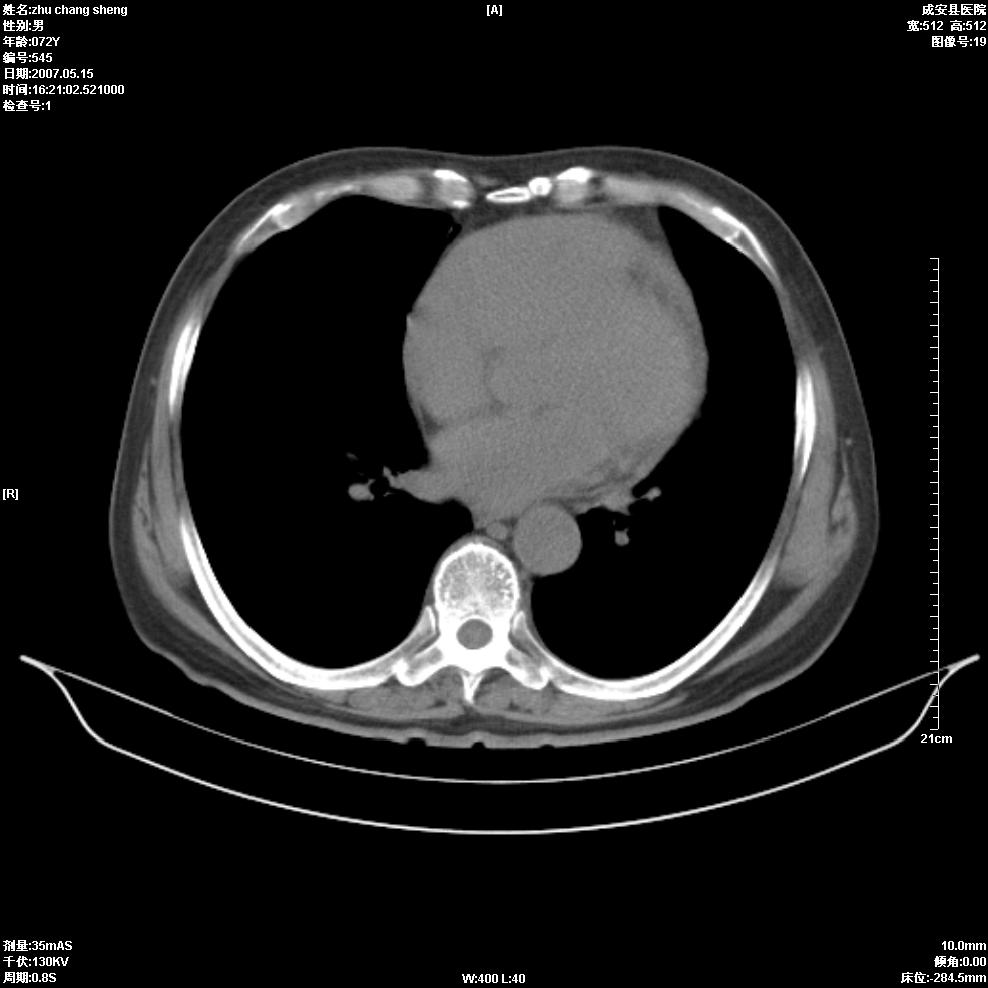

以下是引用医博云天在2007-5-15 19:10:00的发言:[br]心包积液,胸腔积液,心影增大,左心为主。

以下是引用zhangzhongshou在2007-5-15 20:21:00的发言:[br]心包积液可以肯定有,肿块显示不清,建议增强或mri检查。

以下是引用jinning在2007-5-15 21:06:00的发言:[br]心包积液可以肯定,建议增强或mri检查吧!

以下是引用拾荒者在2007-5-15 22:28:00的发言:[br]心包膜增厚,有少量积液,右室前壁示均匀软组织密度影,边界欠清,建议增强扫描或mri检查与室壁瘤鉴别。

以下是引用还珠格格在2007-5-19 9:50:00的发言:[br]病人与5月18日 做了核磁增强扫描 确诊为前上纵隔侵袭性胸腺瘤。